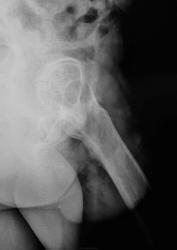

Исход Легг-кальве- пертеса в виде деф. артроза 3.

Жалуется на боли в тазобедренном суставе.

Просветление, и хорошое действительно есть, это не технические моменты, остеопороз и в тазовой кости не хилый, да и на мониторе было видно перестройку структуры. Я про себя, не распространяясь, так, просто так подумал, как "чашку" крепить будут?

Цемента GHV тут надо очень много. И всё-равно может получиться не "как лучше, а как всегда")). CMW - цемент тут не годится, расколется. А бесцементные конструкции ставить вообще никак нельзя. В общем, я бы подписку взял с пациента об отказе от любых претензий - только тогда протез.